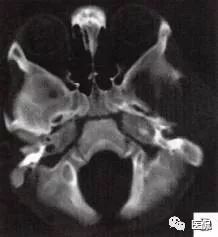

图E、F,横、 矢状位CT增强示软组织肿块轻度均匀强化,两病灶间亦见强化软组织影;

图G,矢状位骨窗示骨质破坏,边缘光整,无硬化边;

图H,为颅骨容积重建,提示类圆形骨质缺损,边缘光滑、整齐。